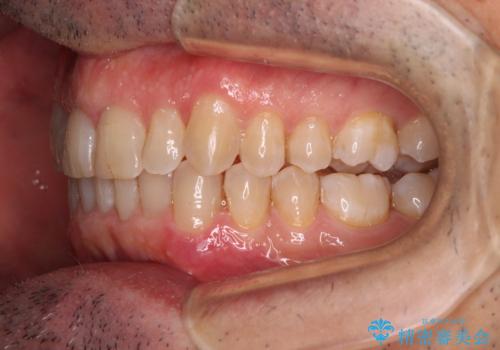

- 前歯のデコボコを気にして来院された患者様です。

インビザラインでもワイヤー装置でも対応可能でしたが、仕事の都合で来院回数を減らしたいとのことでインビザラインによる矯正治療を選択されました。

著しく咬合力が強いため、奥歯がしっかりと噛めずに治療が長引くことが懸念されました。

1セット目のインビザラインを使用した際には左右ともに大臼歯が咬み合っていなかったのですが、2セット目できっちりと仕上げることができました。